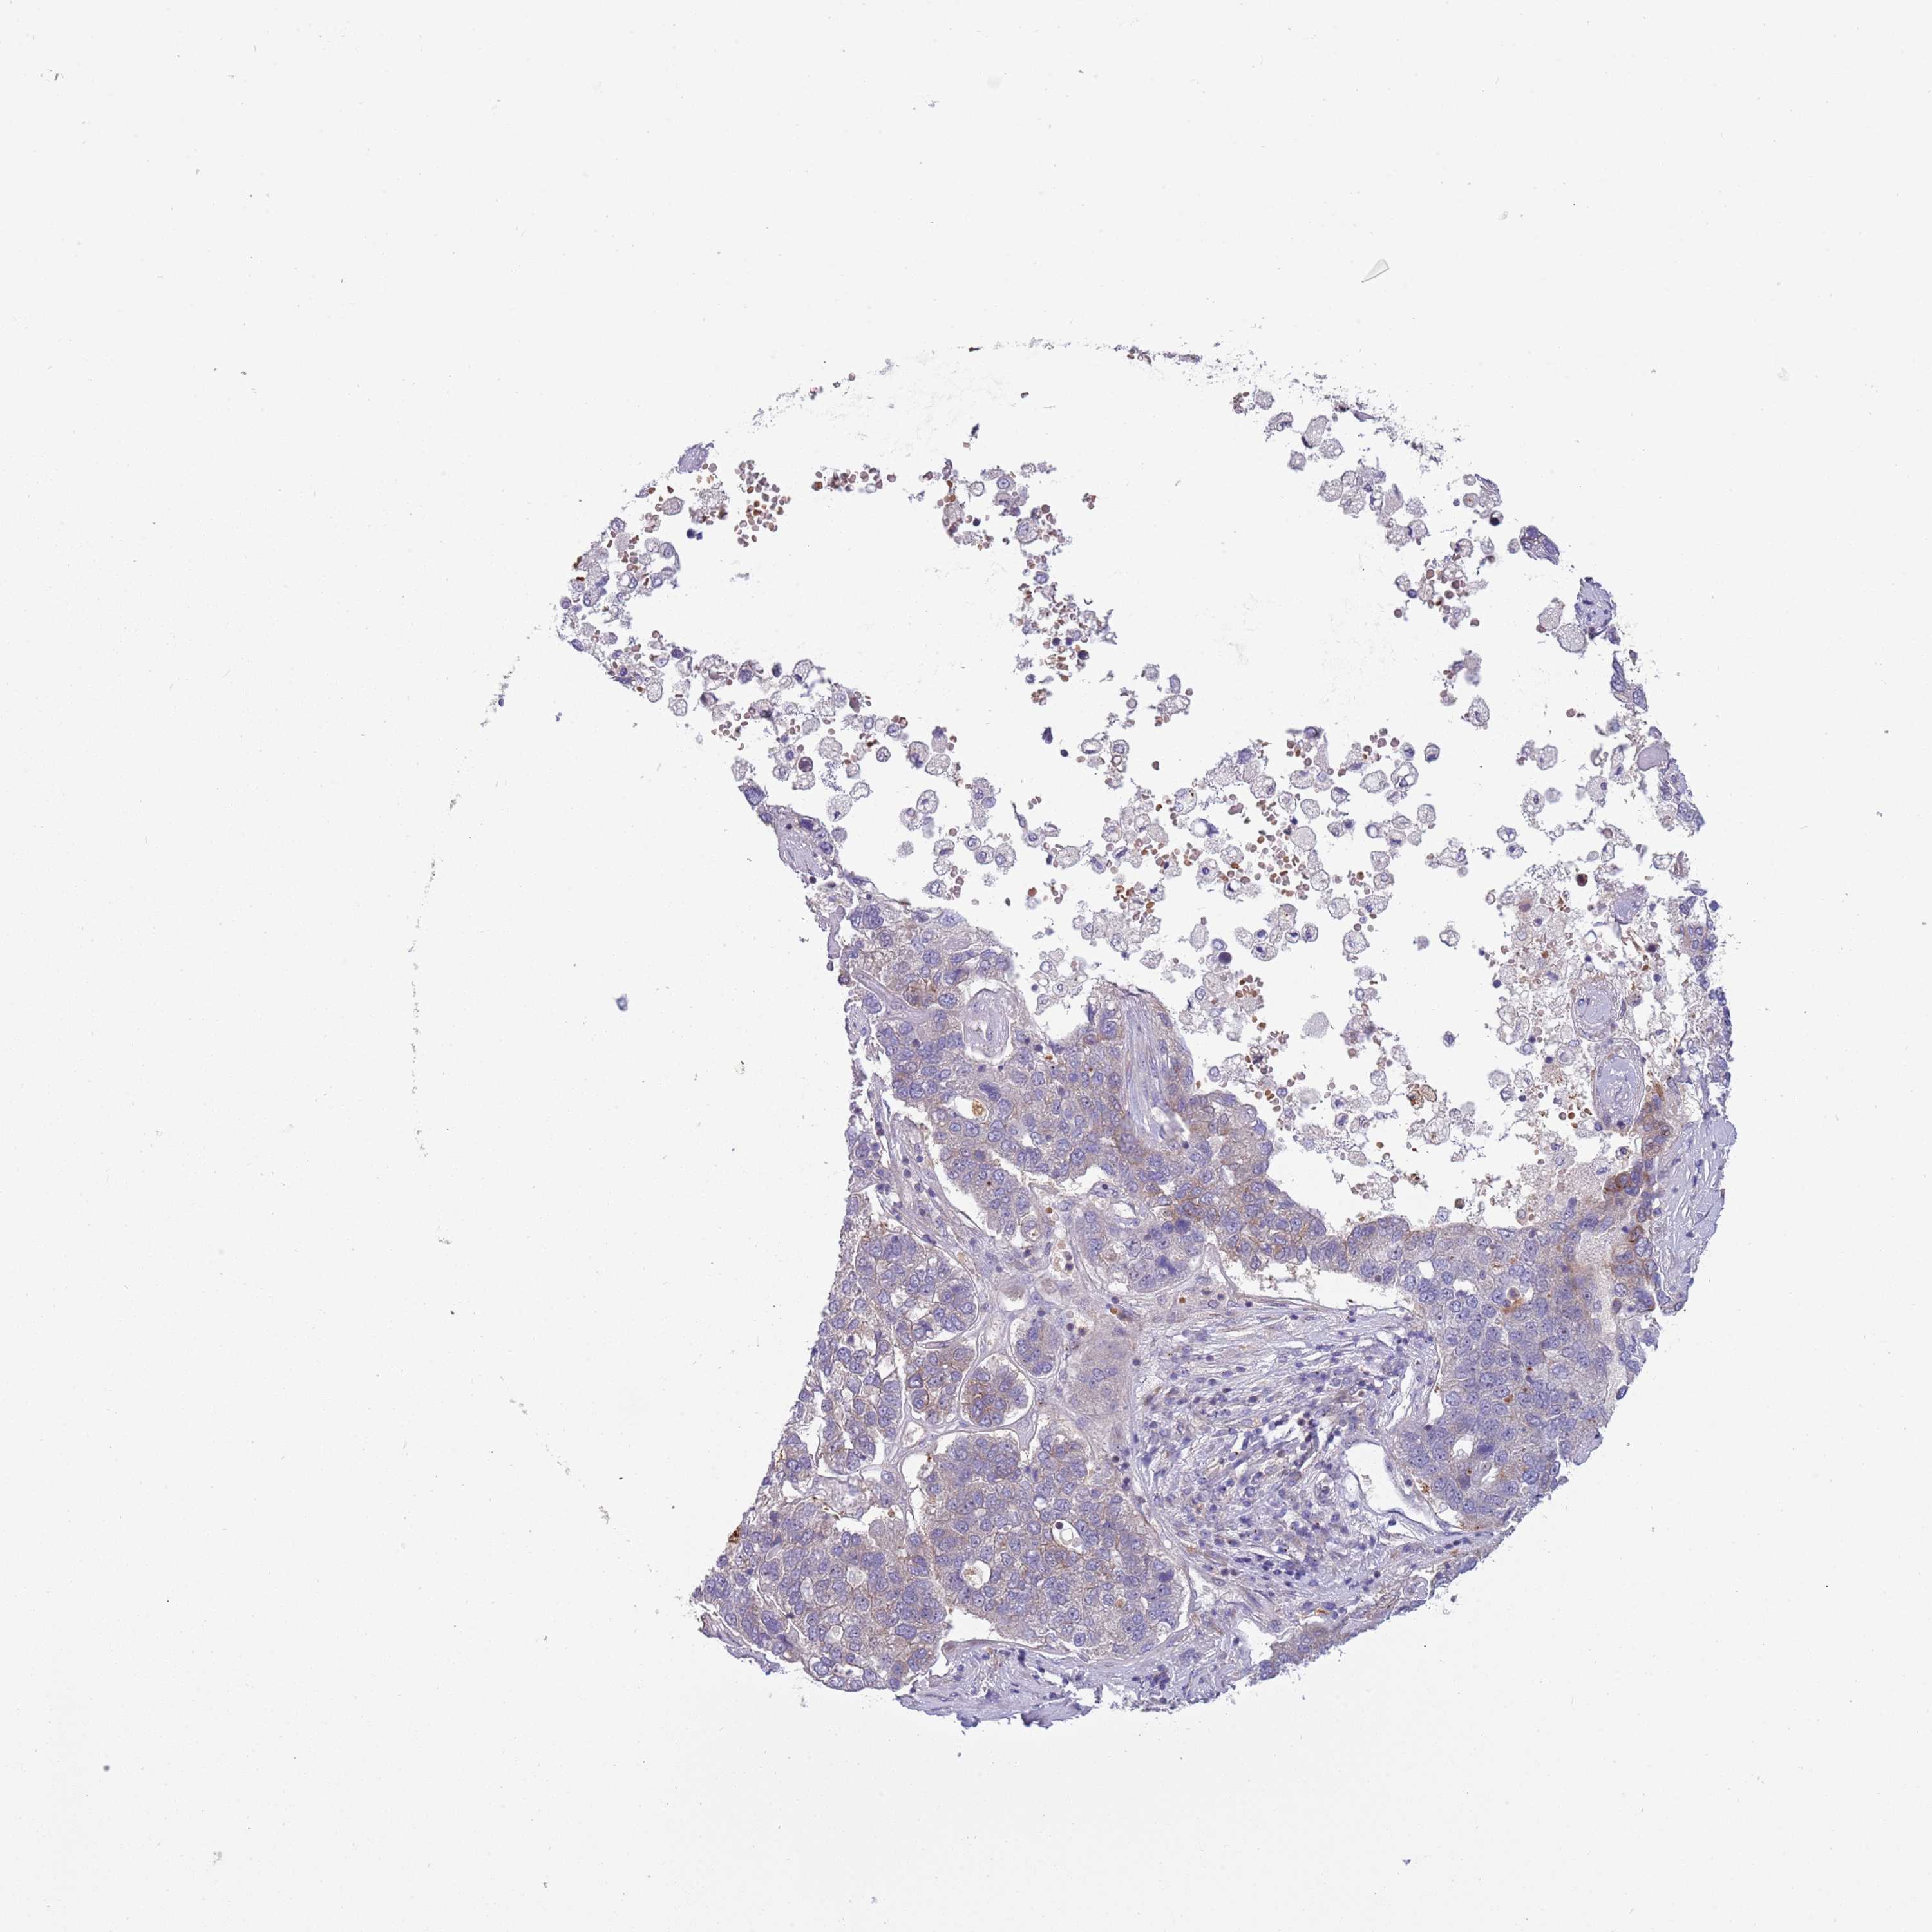

PANCREATIC CANCER - Protein expressioni

A mouse-over function shows sample information and annotation data. Click on an image to view it in a full screen mode. Samples can be filtered based on level of antibody staining by selecting one or several of the following categories: high, medium, low and not detected. The assay and annotation is described here.

Note that samples used for immunohistochemistry by the Human Protein Atlas do not correspond to samples in the TCGA dataset.

Antibody stainingi

Antibody staining in the annotated cell types in the current human tissue is reported as not detected, low, medium, or high, based on conventional immunohistochemistry profiling in selected tissues. This score is based on the combination of the staining intensity and fraction of stained cells.

Each image is clickable and will lead to virtual microscopy that enables deeper exploration of all samples and also displays staining intensity scores, fraction scores and subcellular localization as well as patient and tissue information for each sample.

Antibody HPA023626

Antibody CAB073536

Staining

High

Medium

Low

Not detected

Intensity

Strong

Moderate

Weak

Negative

Quantity

>75%

75%-25%

<25%

None

Location

Nuclear

Cytoplasmic/membranous

Cytoplasmic/membranous,nuclear

Adenocarcinoma, NOS